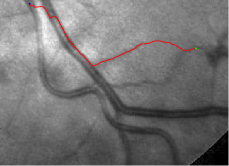

Compare to existing minimal path models. The Riemannian metrics used in [1, 4, 5] are based on the local pointwise information. The curvature-penalized metric [7, 6] and the proposed coherence-penalized metric are able to consider more constraints, i.e., the rigidity for [7, 6] and feature coherence for our metric. These constraints are beneficial to the respective geodesics to reduce the risk of short branches combination problem. Compared to the curvature-penalized metric, our method can be more flexible since the feature map can be produced dependently on the task. In retinal imaging, veins and arteries are distinguishable in terms of gray levels or vesselness values, satisfying the formulation of the proposed model. Especially for vessels with strong tortuosity, the curvature-penalized metric, which favours a smooth curve, fails to catch the expected vessels as shown in the left column of Fig. 2. From the right column of Fig. 2, one can see that our model can obtain a good result.

Validation. We validate our minimal path model on respective 54 and 30 patches obtained from the DRIVE [14, 15] and the IOSTAR [16] datasets with AV groundtruth. Each artery involved in these parches locates near a vein or crossing it at least once. Our goal is to extract the artery between two given points. In order to get the quantitative evaluation, we first convert each continuous spatial path to an 4-connected digital path which is considered as a pixel collection. We denote by the collection of digital path pixels inside the artery groundtruth map . Thus, a measure can be simply defined as , where and mean the respective number of elements involved in and . We compare our model to four existing minimal path models: the isotropic Riemannian (IR) model [1], the anisotropic radius-lifted Riemannian (ArR) model [4], the isotropic orientation-lifted Riemannian (IoR) model [5] and the curvature-penalized (CuP) model [7]. The construction of these metrics are based on the OOF outputs [12]. Note that a centerline-based potential is chosen so that we remove the radius dimension of [5] to reduce computation complexity. The results in terms of the score are presented in Table 1, including the average (Avg.), maximum (Max.), minimum (Min.) and standard deviation (Std.) values. In both DRIVE and IOSTAR datasets, our method can achieve the best performances thanks to the coherence penalization. Note that in Table 1, we evaluate our method by using the refined paths instead of using the original coherence-penalized minimal paths. For comparisons in visualization, we show the minimal paths from the ArR metric , the CuP metric and the proposed coherence-penalized metric on three retinal patches as shown in Fig. 3. The targeted artery vessels which cross veins at least once are labeled by red color in column 1. The paths shown in column 4 from the proposed metric are results after refinement. One can claim that our method indeed can catch expected arteries while other metrics fall into the traps of short branches combination.